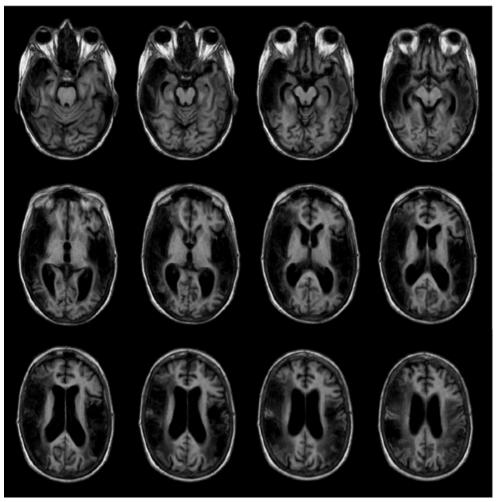

The phenomenon of blindsight has been largely studied and refers to residual abilities of blind patients without an acknowledged visual awareness. Similarly, "deaf hearing" might represent a further example of dissociation between detection and perception of sounds. Here we report the rare case of a patient with a persistent and complete cortical deafness caused by damage to the bilateral temporo-parietal lobes who occasionally showed unexpected reactions to environmental sounds despite she denied hearing. We applied for the first time electrophysiological techniques to better understand auditory processing and perceptual awareness of the patient. While auditory brainstem responses were within normal limits, no middle- and long-latency waveforms could be identified. However, event-related potentials showed conflicting results. While the Mismatch Negativity could not be evoked, robust P3-like waveforms were surprisingly found in the latency range of 600-700 ms. The generation of P3-like potentials, despite extensive destruction of the auditory cortex, might imply the integrity of independent circuits necessary to process auditory stimuli even in the absence of consciousness of sound. Our results support the reverse hierarchy theory that asserts that the higher levels of the hierarchy are immediately available for perception, while low-level information requires more specific conditions. The accurate characterization in terms of anatomy and neurophysiology of the auditory lesions might facilitate understanding of the neural substrates involved in deaf-hearing.

盲视现象已得到广泛研究,指的是失明患者在没有明显视觉意识的情况下残留的能力。同样,“聋听”可能代表了声音检测和感知之间分离的另一个例子。在这里,我们报告了一例罕见的双侧颞顶叶损伤导致的持续且完全的皮质性耳聋患者的病例,尽管她否认自己能听到声音,但她偶尔会对环境声音做出意想不到的反应。我们首次应用电生理技术来更好地理解患者的听觉处理和知觉意识。尽管听觉脑干反应在正常范围内,但无法识别中潜伏期和长潜伏期的波形。然而,事件相关电位的结果却相互矛盾。虽然无法诱发失匹配负波,但令人惊讶的是,在 600-700 毫秒的潜伏期范围内发现了类似 P3 的强波。尽管听觉皮层广泛受损,但类似 P3 的电位的产生可能意味着即使没有声音的意识,也需要有独立的电路来处理听觉刺激,这些电路是完整的。我们的结果支持了反向层次理论,该理论认为,层次结构的较高层次可以立即用于感知,而低层次信息则需要更具体的条件。从解剖学和神经生理学方面对听觉损伤进行准确描述,可能有助于理解参与聋听的神经基质。